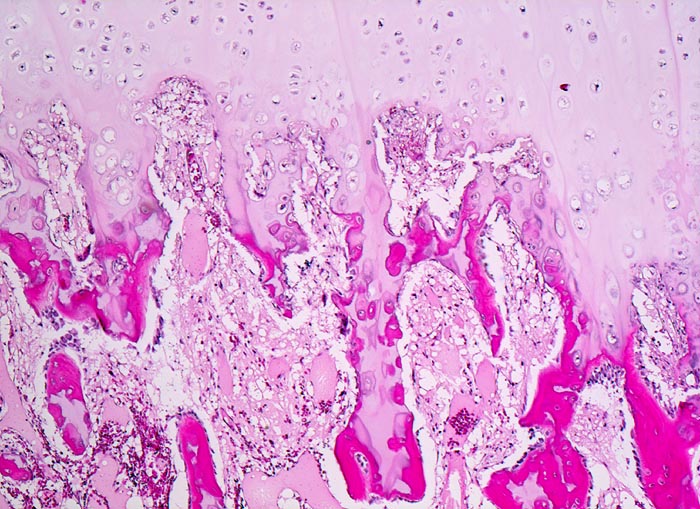

Osteochondrome sind breitbasig dem Knochen aufsitzende oder gestielte knöcherne Tumoren, die von einer 1-6mm dicken Kappe aus hyalinem Knorpel bedeckt werden. Zwischen Knorpel und Knochen liegt eine Zone enchondraler Ossifikation, die der normalen Wachstumsfuge ähnelt und den Ausgangspunkt für die Grössenzunahme des Tumors bei noch nicht abgeschlossenem Skelettwachstum darstellt. Der hyaline Knorpel wirkt etwas unorganisiert und ist bedeckt von einer dünnen Schicht Perichondrium.

• Kappenförmiges hyalines Knorpelgewebe ohne Zellatypien sitzt auf einem knöchernen Stiel. Die Knorpelkappe ist 2mm dick.

• Knorpelkappe bedeckt von einem schmalen Saum zellarmen Bindegewebes (=Perichondrium).

• Übergang des Knorpels in enchondrale Ossifikationszone wie in einer Epiphysenfuge: Knochen wird abgelagert entlang von linearen Knorpelsäulen.